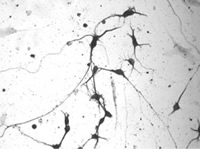

Amyotrophic Lateral Sclerosis or ALS, is a chronic, progressive disease marked by gradual degeneration of the nerve cells in the central nervous system that control voluntary muscle movement. The disorder causes muscle weakness and atrophy; symptoms commonly appear in middle to late adulthood, with death in two to five years. The cause is unknown, and there is no known cure. Also called Lou Gehrig's Disease, or Motor Neuron Disease.

Alpha lipoic acid (ALA) serving size should be around 250mg taken 2 to 4 times per day. Acetyl-l carnitine greatly improves the effects on repairing nerve and other tissue damage and works synergistically with ALA. Creatine may also help. There are now available a few ALA-carnitine combination supplements including one by NSI. These types are made to combat nerve degeneration and may help in disorders such as ALS, Alzheimer's, and MS.